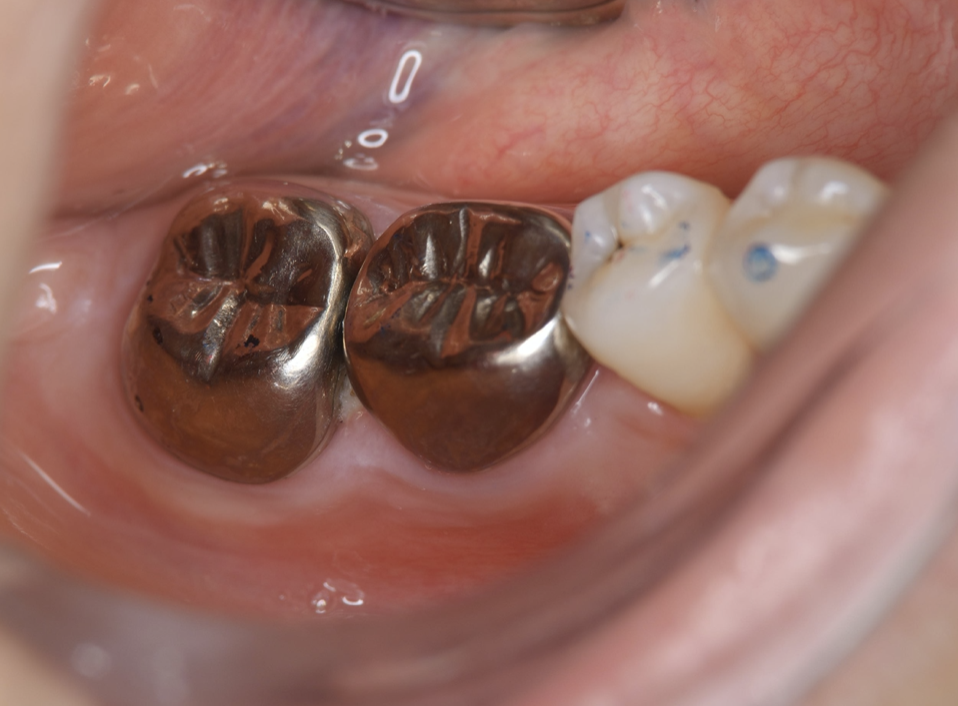

Full metal crowns were inserted for #46 and #47. Pathological mobility and bleeding on probing were not seen, and the transplanted tooth showed good function.

Endodontic treatment was initiated at 14 days after transplantation (8, 17). Root canal treatment for #48 was performed using Ni-Ti files (Pro Taper Next, Dentsply Sirona, Tokyo, Japan) to accommodate the complex morphology of the root canal and for minimal removal of the tooth structure during formation of the access cavity. Root canals were medicated with calcium hydroxide paste and then filled with gutta percha. The splint was also removed four weeks after the operation and a resin core was used as an abutment construction. In an attempt to appropriately modify contact and the crown morphology, a crown prosthesis was made with a full metal crown, with occlusal contact confirmed with use of a temporary crown and easy to visualize markings on occlusal paper. The full metal crown was cemented six months later (Figure 7).

Figure 7.Inter-oral photo obtained after treatment. Full metal crowns were inserted for #46, #47. Pathological mobility and bleeding on probing were not seen, and the transplanted tooth showed good function.